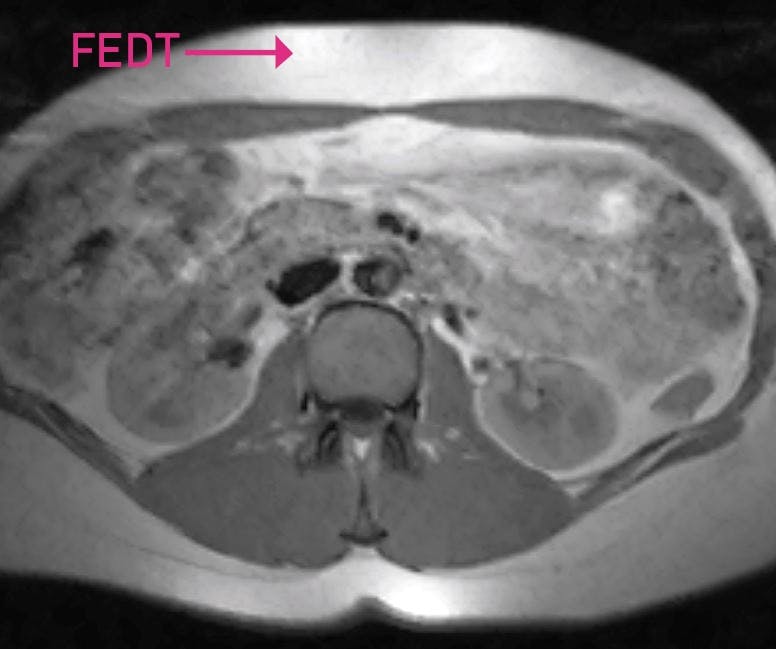

MAVEFEDT MELLEM INDVOLDENE Tværsnit af mave. Personen her har både meget mavefedt (det hvide) lige under huden og inde mellem indvoldene.